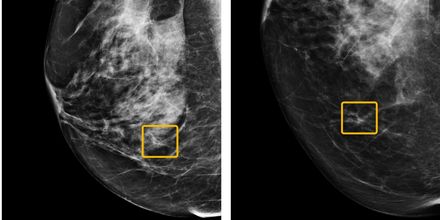

Google har en AI som kan upptäcka bröstcancer Gör detta bättre än mänskliga läkare Googles AI-företag Deep Mind har utvecklat ännu en artificiell intelligens och deras senaste AI har man tränat upp för att upptäcka bröstcancer på patienters mammografi-bilder. I tester ska Deep Minds AI ha kunnat avgöra om en patient hade bröstcancer lika bra som professionella radiologer. I vissa fall där mänskliga läkare trott att patienten hade cancer eller hade missat att patienten hade cancer ska AI:n bättre ha kunnat diagnosticera patienten. Artificiella intelligenser som den Googles Deep Mind nu har tagit fram kommer sannolikt att bli vanligare inom vården i framtiden även om de än så länge inte används i någon direkt utsträckning. Än så länge är det även mänskliga läkare som har sista ordet när det kommer till att diagnosticera patienter men AI:s som den här kommer sannolikt att underlätta läkares arbete i framtiden. Tumnagel